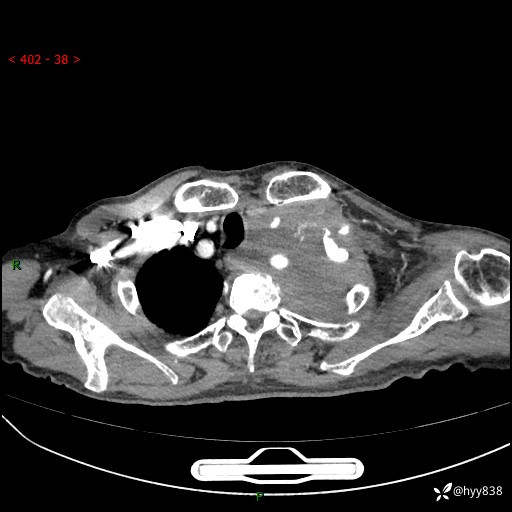

老年男性,气促5月,胸背痛2月。发现肺尖较大肿块,摧枯拉朽之势---结果公布~

现病史:患者于5月前饮酒后突发静息状态下气促不适,无胸闷、胸痛、发热、咳嗽、咳痰等不适,于当地第五人民医院及我院就诊,输液治疗后(具体不详)后气促稍缓解,遂出院后自行口服中草药治疗。近2月出现胸背痛,伴左上肢疼痛、乏力、感觉异常,稍有咳嗽、咳痰,咳黄痰、痰液粘稠,无咳血。为进一步诊治来我院。

胸部CT增强扫描(外院平扫)